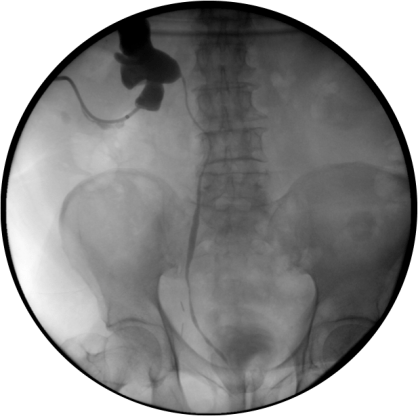

TRATAMIENTO.

Se realiza una nefrostomía percutánea para drenar el contenido infectado alojado en el interior del sistema colector urinario.